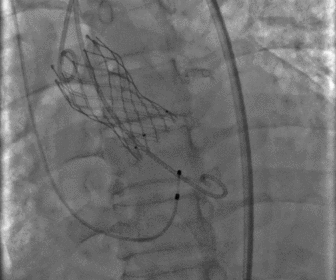

瓣膜释放完毕

图片

股动脉术后造影

术后结果

术后造影及超声探查未见瓣周漏,跨瓣压差术前54mmHg,术后降为0mmHg,术中及术后未出现相关并发症,手术圆满完成。